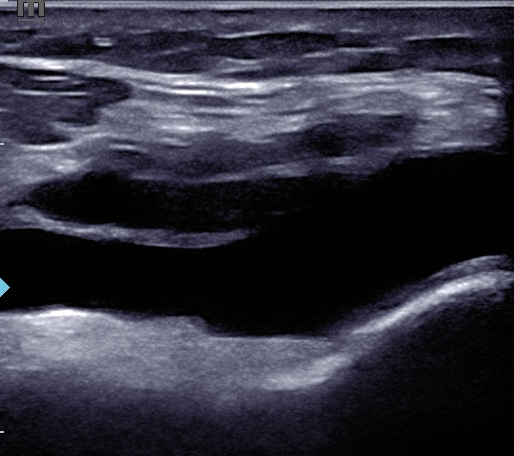

En la ecografía se observan signos de extrusión meniscal y degeneración intrasustancia del menisco externo, así como un quiste de Baker sin signos de rotura. Se observa derrame articular a nivel de receso suprapatelar. No alteraciones relevantes en otras estructuras. Se descarta TVP mediante compresión simplificada.

Meniscopatía con extrusión meniscal y Quiste de Baker asociado.

Ha sido valorado por COT, quien solicita RMN donde se objetiva rotura radial completa de menisco externo, con ligera elongación de LCA y presencia de quiste de Baker. Ha sido admitido en la lista de espera quirúrgica.

La exploración física en la gonalgia no siempre permite identificar el origen del dolor. La ecografía es un buen complemento e identifica lesiones que se pasan que en ocasiones podrían pasar desapercibidas. Además descarta signos de alarma o complicaciones, como una TVP o una rotura del quiste de Baker.